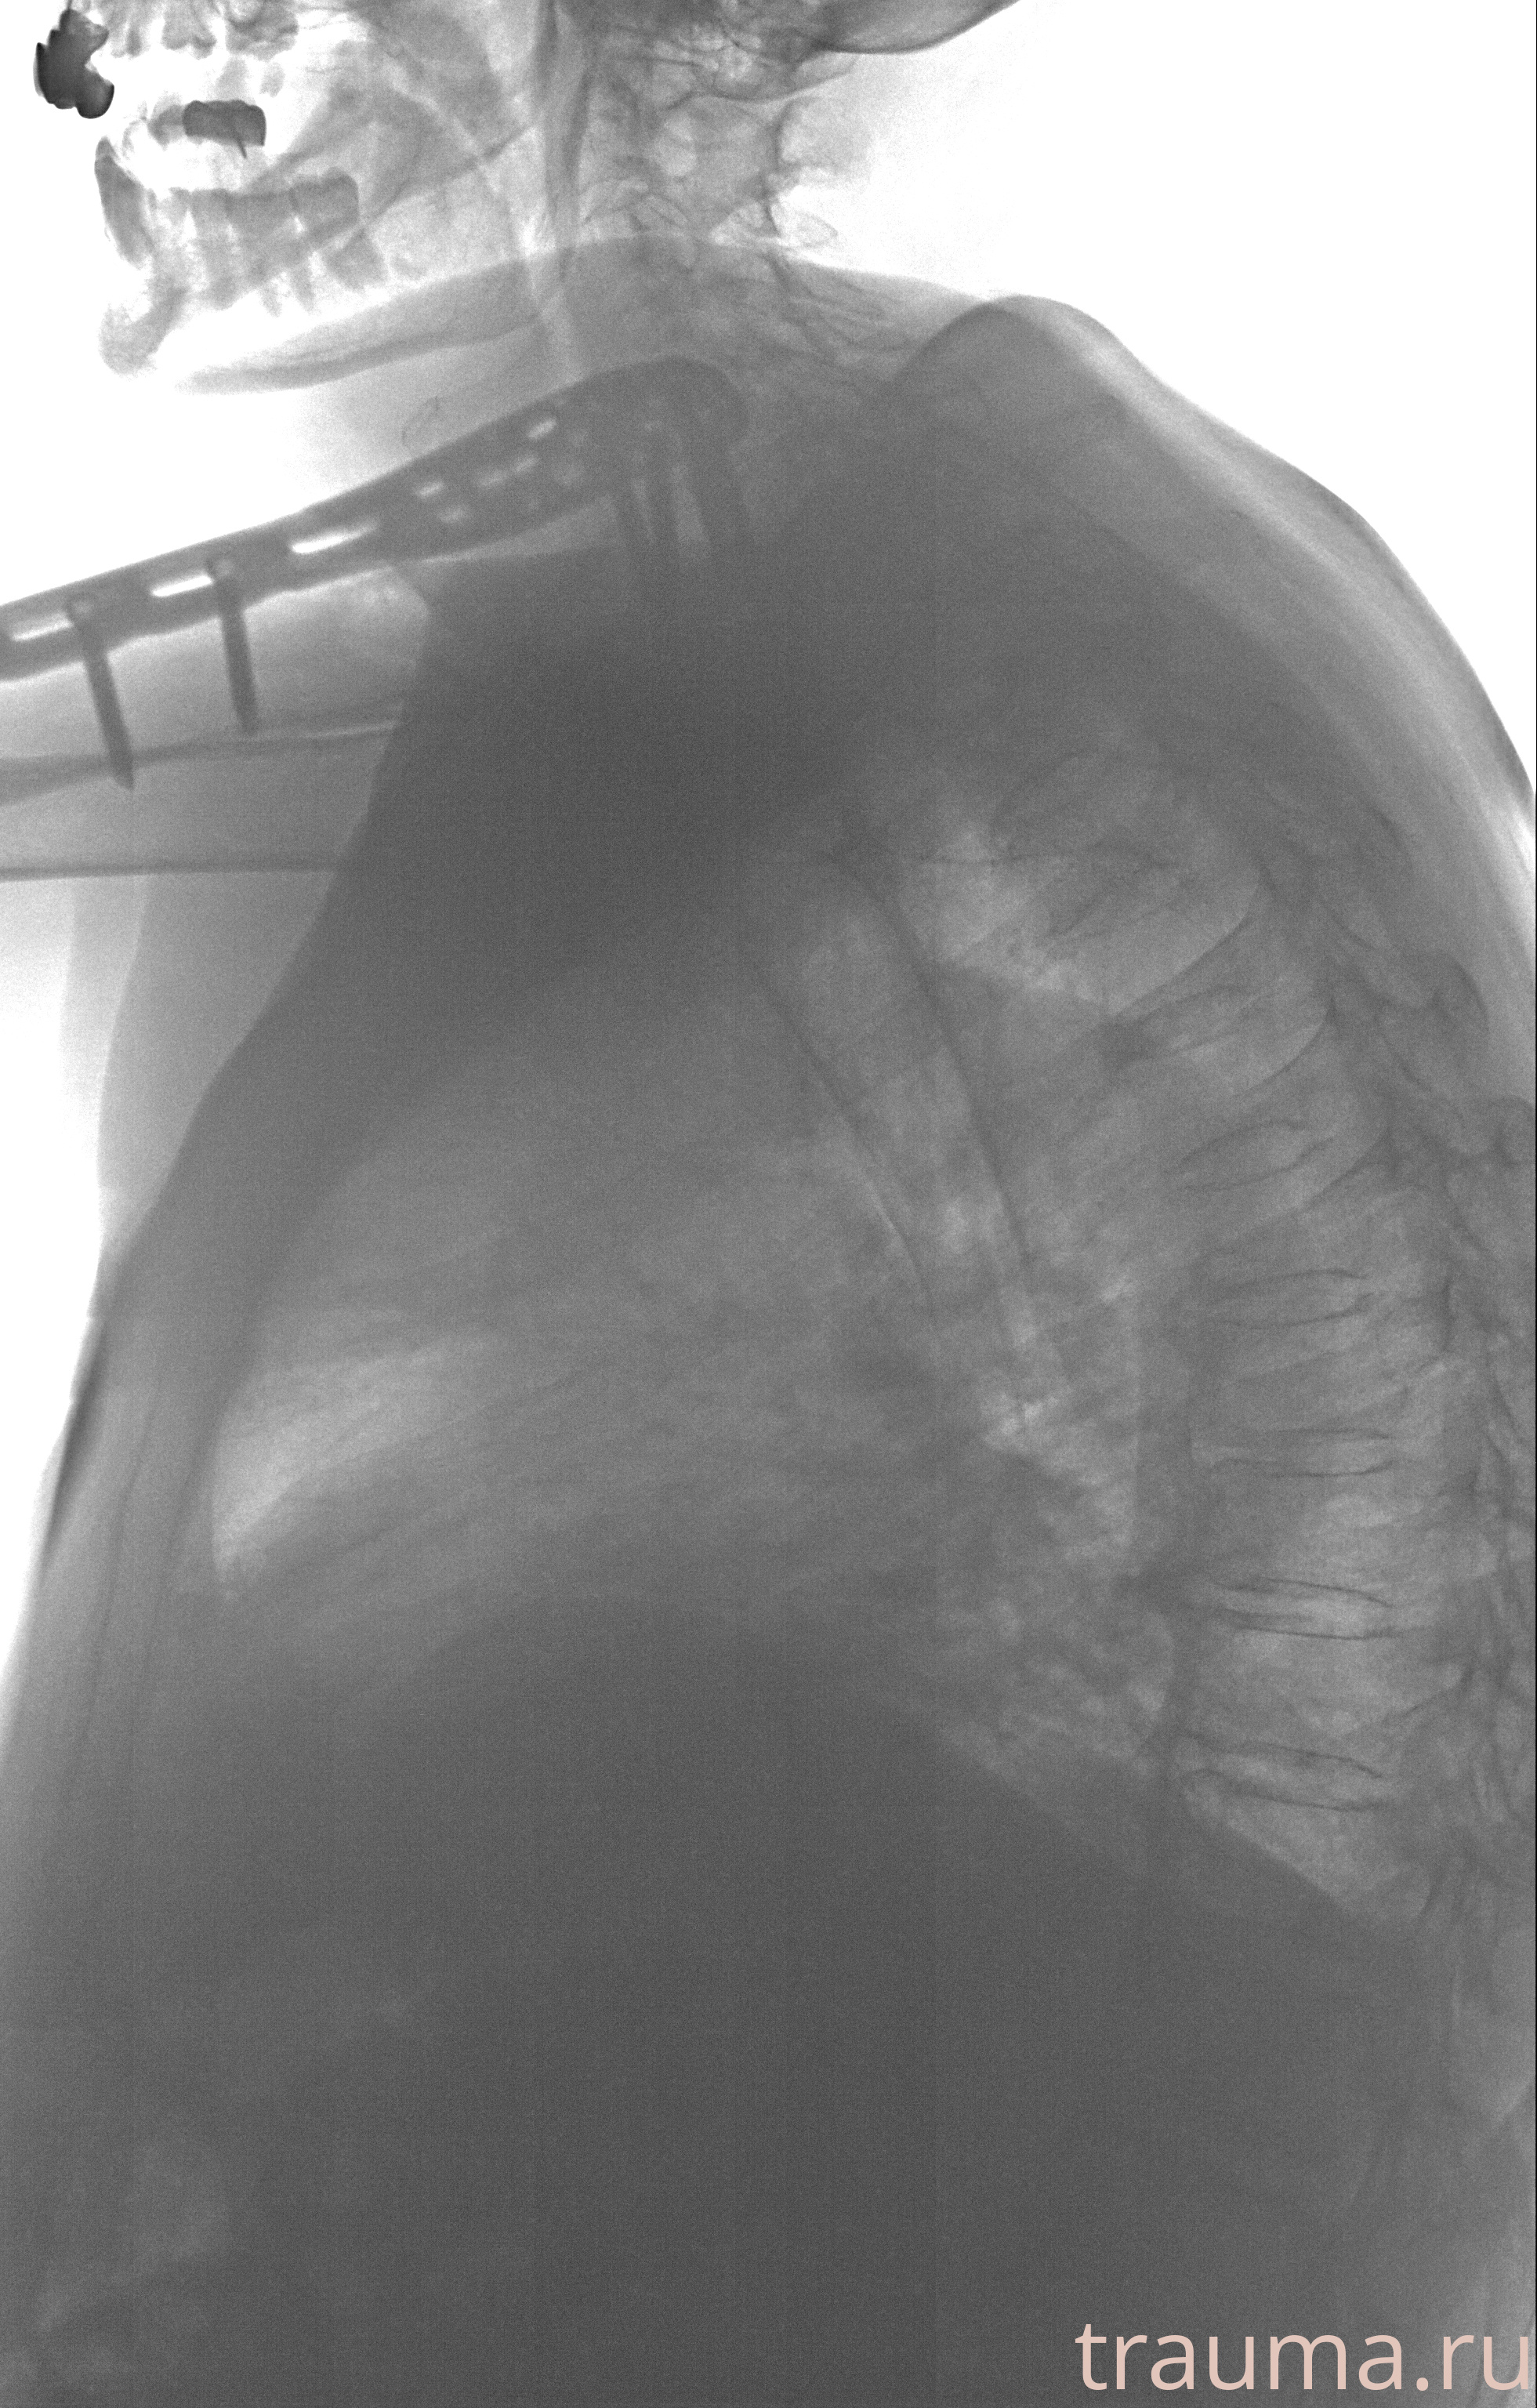

Рентген на дому: по вашему адресу приезжает врач-рентгенолог, травматолог-ортопед с мобильным рентгеновским аппаратом, проводит диагностику травмы или заболевания, делает необходимые рентгенограммы, дает рекомендации по дальнейшему лечению. Получить качественные снимки в домашних условиях возможно благодаря уникальной методике, разработанной МосРентген Центром для института  Склифосовского